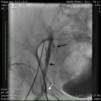

A 4F sheath was first placed into the left femoral artery with the patient supine, and then the patient was placed in a prone position. After obtaining an angiogram of the left lower extremity, the popliteal artery was accessed under fluoroscopic guidance and a short 6-cm 6F sheath was placed. After adequate anticoagulation was achieved with heparin, a Confianza pro 12 wire (Asahi Intecc, Nagoya, Japan) was used to cross the CTO with support from a Trailblazer support catheter (ev3, Plymouth, MN), which appeared to be in the true lumen of the SFA until the proximal to ostial SFA, from where it went into multiple dissection planes. Then, the Confianza pro 12 wire was replaced by a 0.035 Glidewire Advantage wire (Terumo Interventional Systems, Somerset, NJ), which also went to different dissection planes; there was a collateral vessel at the proximal SFA extending to the external iliac artery.

An angiogram from the left femoral sheath at this time showed retrograde filling of the distal and proximal SFA (Figure 4) and then the dissection plane in the EIA with a wire tip perforation and bleeding (Figures 5 and 6) to the retroperitoneal region at the external iliac artery with displaced bladder (Figure 6). Protamine was given to reverse the heparin and a 7-minute balloon inflation was performed in the distal SFA using a 5.0 mm×40 mm Evercross balloon (ev3, Plymouth, MN) to stop the retrograde bleeding. On repeat angiography, the distal SFA CTO was reoccluded and the dissection plane appeared to be sealed, with no further bleeding into the retroperitoneal region (Figures 7 and 8). Other than mild nausea after protamine, the patient reported no major symptoms during this procedure. When activated coagulation time was 130 s, the femoral and popliteal sheaths were removed. A 3-g/dl drop in hemoglobin was noted after the procedure that remained stable over the next two days. Popliteal and pedal pulses were palpable and unchanged following the procedure.